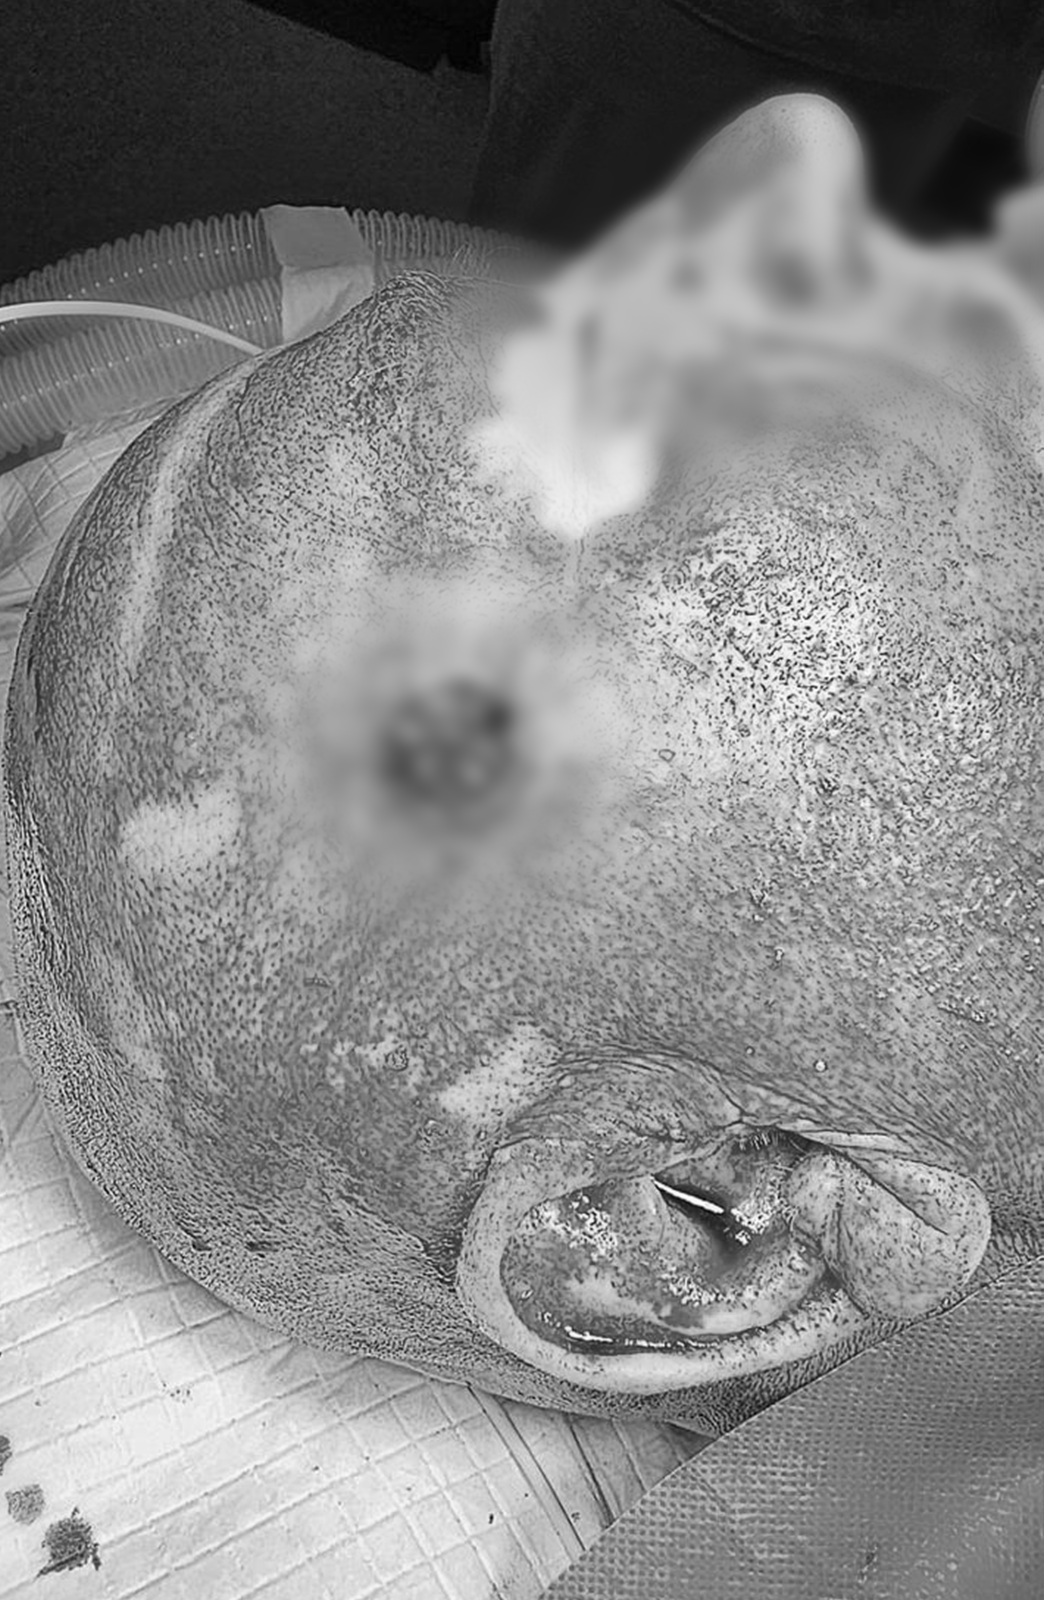

Un pacient cu multiple comorbiditǎți s-a prezentat în spitalul nostru pentru consultație primarǎ în serviciul de dermatologie, având o formațiune tumorală de mari dimensiuni situatǎ la nivelul scalpului în regiunea temporalǎ. În urma examenului dermatoscopic, pacientul a primit diagnosticul de carcinom spinocelular, reprezentând un tip agresiv de cancer de piele.

Printre factorii care ar fi putut contribui la apariția acestei patologii se numără: expunerea la razele ultraviolete o lungă perioadă de timp, apariția keratozei actinice, precum și îmbătrânirea structurilor pielii la acest nivel. Datoritǎ dimensiunii crescute a acestei formațiuni, aproximativ 8 cm, pacientul a fost îndrumat cǎtre departamentul de Chirurgie Oralǎ şi Maxilo-facialǎ a spitalului nostru.

Intervenția chirurgicalǎ a fost una amplǎ, din cauza extensiei tumorii în straturile de sub piele (țesut celular subcutanat), până la nivelul mușchiului temporal.

Astfel, Conf. Dr. ȚENȚ ANDREI, medic primar chirurgie oralǎ şi maxilo-facialǎ a efectuat rezecția formațiunii tumorale în limite de siguranțǎ oncologicǎ, practicând şi reconstrucția plastic a defectului cu 2 lambouri de vecinǎtate – unul insular din regiunea obrazului avansat în defect şi un lambou de scalp parietal translat în defect prin rotație regiunii parietale tegumentare. În consecință, fizionomia pacientului, conturul urechii, pleopelor, sprâncenelor vor fi nemodificate datorită lipsei de tensiune în sutură. Intervenția a fost efectuată cu ajutorul echipei de anestezie și terapie intensivă condusă de către Sef Lucrări Dr. BIMBO ERIKA, medic primar Anestezie și terapie intensivă și șef de secție ATI a spitalului nostru împreună cu dr. BERES ZSOLT, medic Anestezie și Terapie intensivă.